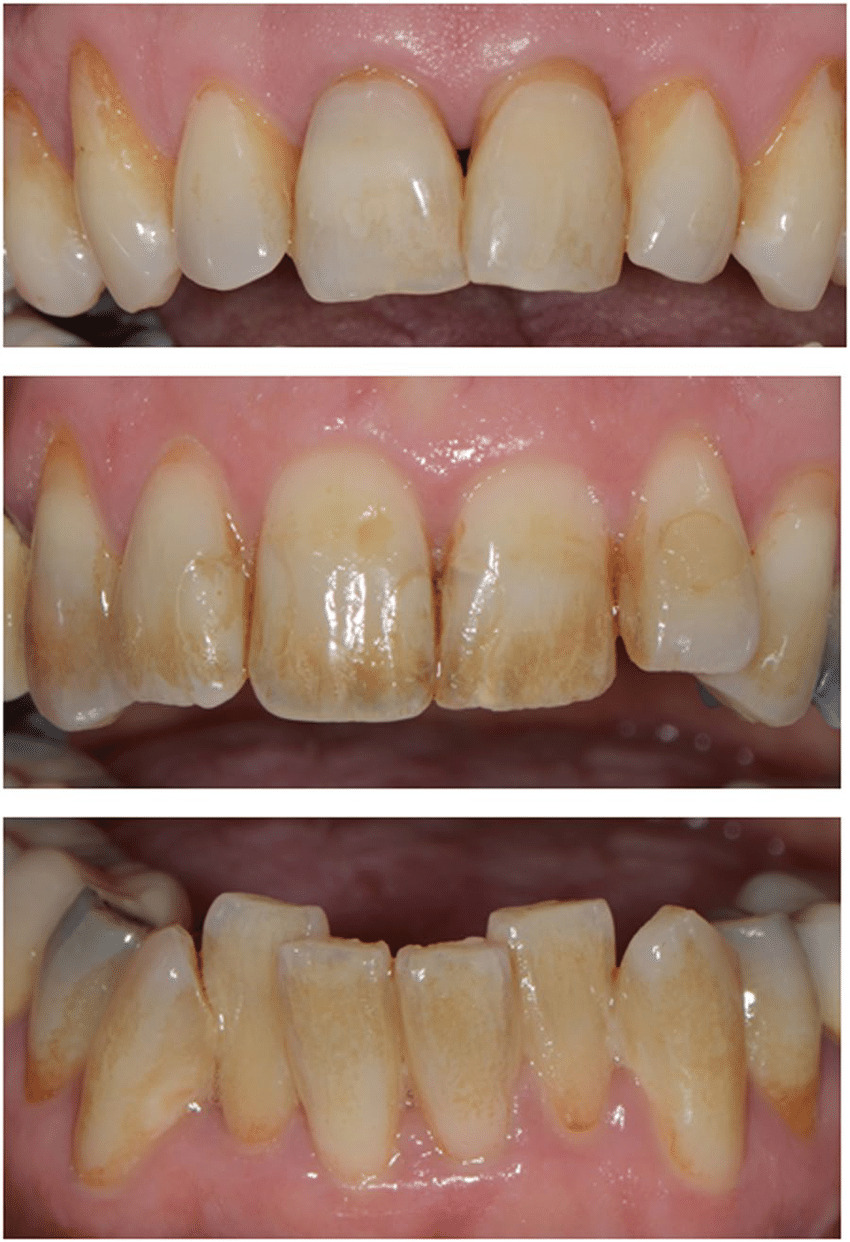

عندما تنظر في المرآة قد تلفت انتباهك تلك السن الوحيدة التي تبدو أغمق لونا من بقية أسنانك مما يؤثر على جمال ابتسامتك وثقتك بنفسك. قد تتساءل بقلق: هل هذا التغير في اللون ناتج عن علاج عصب قديم؟ هل هو نتيجة صدمة تعرضت لها السن؟ والأهم من ذلك هل يمكن استعادة لونها الطبيعي دون اللجوء إلى خيارات معقدة ومكلفة مثل الفينير أو التيجان؟ الإجابة تكمن في إجراء دقيق ومحافظ يُعرف باسم التبييض الداخلي للأسنان (Internal Bleaching). هذا الإجراء الذي يعود تاريخه لأكثر من 150 عاما قد تطور بشكل كبير ليصبح اليوم واحدا من أكثر الحلول فعالية وأمانا لاستعادة اللون الطبيعي للأسنان غير الحية. في هذا الدليل الشامل سنستعرض كل ما تحتاج إلى معرفته حول التبييض الداخلي للأسنان بدءا من أسبابه وأنواعه وصولا إلى خطواته الدقيقة النتائج المتوقعة ومستوى الأمان الذي يوفره وكيف يمكن لخبرائنا في مجمع "رها" مساعدتك في تحقيق أفضل النتائج الممكنة.

التبييض الداخلي للأسنان هو إجراء تجميلي محافظ يهدف إلى تفتيح لون سن واحدة غير حية (Non-vital tooth) أي سن خضعت لعلاج العصب (المعالجة اللبية) وفقدت حيويتها. على عكس التبييض الخارجي الذي يطبق على السطح الخارجي لجميع الأسنان يتم هذا الإجراء عن طريق وضع مادة التبييض داخل حجرة العصب الفارغة لتفتيح لون السن من الداخل إلى الخارج. الهدف الأساسي هو إزالة التصبغات العميقة الموجودة داخل طبقة العاج والتي لا يمكن للطرق التقليدية الوصول إليها .

لا يمكن استخدام التبييض الداخلي لجميع حالات تغير اللون بل هو مخصص لحالات محددة جدا. يعد هذا الإجراء مثاليا عندما يكون لديك سن واحدة داكنة بعد أن خضعت لعلاج العصب. الأسباب الرئيسية التي تجعل التبييض الداخلي هو الخيار الأمثل تشمل:

لماذا يتغير لون الأسنان من الداخل؟

يعود تغير اللون الداخلي للأسنان (Intrinsic Discoloration) إلى دخول مواد ملونة (Chromogens) إلى بنية السن الداخلية وتحديدا طبقة العاج وتراكمها داخل الأقنية العاجية الدقيقة. هذا النوع من التصبغ لا يمكن إزالته بالتنظيف العادي أو التبييض الخارجي. الأسباب الأكثر شيوعا تشمل:

تغير اللون بسبب علاج العصب

بعد علاج العصب قد تبقى بعض بقايا أنسجة العصب أو الدم داخل حجرة العصب أو قنواته. مع مرور الوقت تتحلل هذه المواد العضوية وتطلق مركبات ملونة تتسرب إلى العاج المحيط مما يؤدي إلى ظهور لون داكن يتراوح بين الرمادي والبني. بالإضافة إلى ذلك بعض مواد حشو قنوات الجذر القديمة مثل تلك التي تحتوي على الفضة يمكن أن تتسبب في تصبغ رمادي للسن مع مرور الوقت .

النزيف الداخلي داخل السن بعد إصابة (Trauma)

تعد الصدمات والإصابات التي تتعرض لها الأسنان من الأسباب الرئيسية لتغير لون سن واحدة. يمكن أن تسبب الصدمة نزيفا داخل حجرة العصب (Intrapulpal Hemorrhage). تتسرب كريات الدم الحمراء إلى الأقنية العاجية ومع تحللها يتم إطلاق الحديد من جزيئات الهيموجلوبين. يتحد هذا الحديد مع منتجات التحلل الأخرى مثل كبريتيد الهيدروجين الذي تنتجه البكتيريا مكونا كبريتيد الحديد الأسود وهو ما يعطي السن لونها الداكن المميز . في دراسة أجريت في نيجيريا وجد أن موت العصب (Pulpal Necrosis) والذي غالبا ما يكون نتيجة لصدمة يمثل 86.8% من حالات تغير لون الأسنان التي يبلغ عنها المرضى .

تحلل العصب أو بقايا الحشوات القديمة

في حال موت العصب وعدم علاجه لفترة طويلة تبدأ أنسجة العصب بالتحلل. هذه العملية تنتج مركبات بروتينية متحللة وسموم بكتيرية تتسرب بعمق في العاج مما يمنح السن لونا رماديا أو بنيا باهتا . كما أن ترك بعض مواد الحشو القديمة مثل حشوات الأملغم بالقرب من السطح الداخلي للسن يمكن أن يتسبب في تسرب أيونات معدنية إلى العاج مما يؤدي إلى تصبغ دائم.